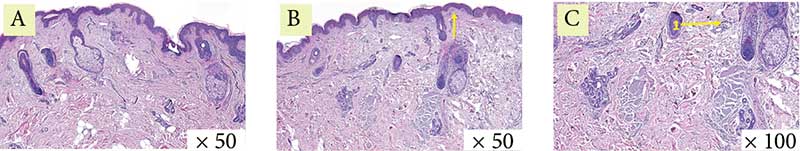

Рис. 1. Пациентка 1. Окраска гематоксилин-эозином: A – до процедуры, B и C – через месяц после процедуры (стрелки указывают на участки с лимфоцитарной инфильтрацией)

Гистологически в эпидермисе отмечается уменьшение гиперкератоза, сглаживание эпидермальных гребней. В дерме отмечены выраженные лимфоцитарные инфильтраты, что свидетельствует о незавершенном воспалительном процессе, а также единичные участки с увеличенным количеством упорядоченных коллагеновых волокон, что говорит о начале и продолжении синтеза коллагена и его реорганизации. Признаков фиброза не отмечено (рис. 1–3).